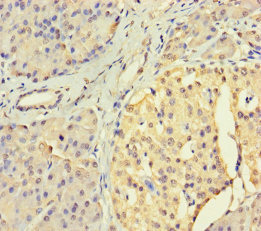

Immunohistochemistry of paraffin-embedded human ovarian cancer using CSB-PA896756LA01HU at dilution of 1:100